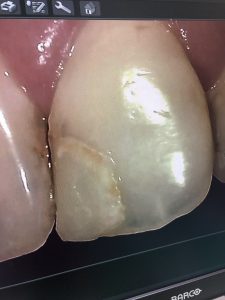

その中でも、オムニクロマと言うコンポジット充填剤が今使われてきています。

オムニクロマ充填剤は、歯の色と同化する性質を持った充填剤です。

今までの充填剤は、何種類かの色を選んで充填していましたが、オムニクロマは色が歯の色と同化してしまうので色を選ぶ必要がないのです。

前歯部や臼歯部にも使用でき、詰め物しているのがわからないくらいです。